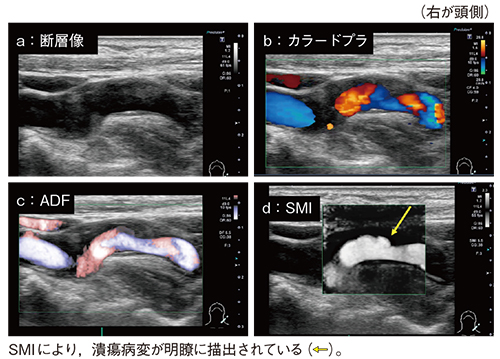

また,SMIでは血管の内腔面と壁との境界を明瞭に描出可能である。断層像やカラードプラはもとより,ADF(Advanced Dynamic Flow)でも描出が不十分であった頸動脈の潰瘍病変が,SMIでは明瞭に描出されている(図5)。

図5 SMIによる頸動脈潰瘍病変の描出能の向上